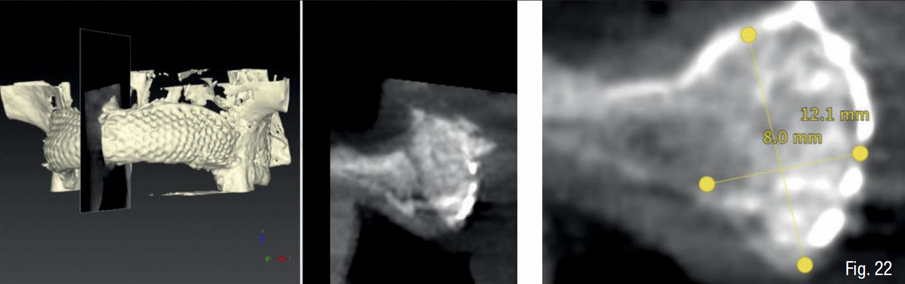

Infine, è stata eseguita un’attenta chiusura di prima intenzione dei lembi chirurgici, mediante una sutura a doppio strato, costituita da una linea di punti a materassaio orizzontale e da una linea di punti staccati singoli, per garantire una chiusura ermetica della ferita (SERAFAST 5/0, Serag-Wiessner, Naila, Germany) (Figg. 18, 19). Nei 7 giorni consecutivi il paziente ha proseguito la terapia antibiotica a base di amoxicillina e acido clavulanico e una terapia antiinfiammatoria a base di nimesulide; risciacqui con clorexidina 0.20% 3 volte al giorno per 2 settimane; e non ha utilizzato la protesi parziale rimovibile sempre per 2 settimane. Dopo 9 mesi, essendo stata confermata una sufficiente mineralizzazione del volume osseo al di sotto della griglia mediante una CBCT post-operatoria (Figg. 20-22), è stata pianificata una chirurgia computer-guidata per inserire gli impianti in modo protesicamente guidato (Figg. 23, 24).

Durante la fase di chirurgia implantare, è stata inizialmente fissata la dima chirurgica sfruttando l’appoggio dento-mucoso; successivamente, è stata eseguita un’incisione lineare crestale e si è proceduto al sollevamento di un lembo vestibolare a tutto spessore e alla rimozione delle mini-viti e della griglia, che essendo osteointegrata in diversi punti è stata rimossa in diversi frammenti. La percentuale di rigenerazione, ovvero il rapporto tra il volume osseo rigenerato e il volume osseo pianificato, è stato calcolato essere del 96% (Figg. 25-29). La dima chirurgica è stata riposizionata e fissata nuovamente mediante i pin di fissaggio precedente preparati, non avendo più il supporto mucoso. Usando una tecnica di sotto-preparazione, sono stati realizzati i siti implantari e sono poi stati inseriti i 6 impianti programmati: 4 impianti dritti con dimensione 10 x 3.7 mm e 2 impianti angolati a 25° con dimensione 12 x 3.7 mm, al fine di evitare il seno mascellare (BTK implant Isy+, Biotec Srl, Dueville, Vicenza, Italy) (Fig. 30).